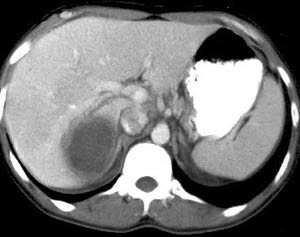

到了医院,一番检查下来,一个令人震惊的事实摆在面前:他的肝上有一个巨大的囊肿。

按照医生的说法:正是因为这个囊肿的迅速生长,才导致他突然肝区疼痛的。

【知识点】阿米巴肝脓肿是由于溶组织阿米巴滋养体从肠道病变处经血流进入肝脏的。肠道阿米巴病主要由于食入被包囊污染的食物或水而引起。但是,大家也不要过于担心:阿米巴包囊对热和干燥较敏感,加热50℃几分钟即被杀死。因此,只要做到尽量吃熟食以及注意个人卫生就可以了。